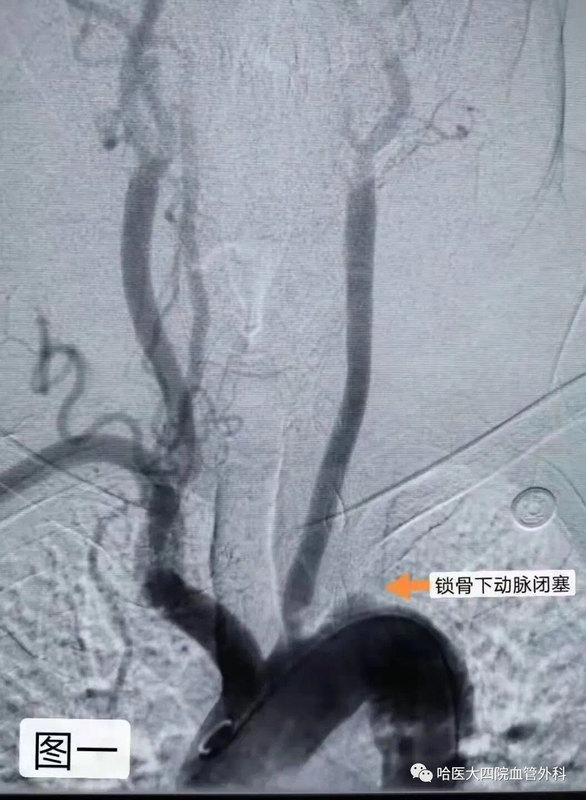

?家住綏化市的李大爺在一個月前發(fā)現(xiàn)自己左上肢血壓較右上肢低,左上肢脈搏觸摸不清,左上肢無力,并伴有頭暈、頭疼的癥狀。近一周癥狀逐漸加重,并出現(xiàn)左側(cè)手指涼麻及左手活動受限等癥狀。為求明確病因,家屬帶李大爺來到了哈醫(yī)大四院找到黃任平教授。???????黃任平主任查體后發(fā)現(xiàn)患者左上肢皮溫低于右上肢,左上肢橈動脈搏動十分微弱,左上肢血壓比右上肢低了一大截。進一步行血管彩超回報患者左側(cè)鎖骨下動脈竊血,考慮鎖骨下動脈起始段完全閉塞,CTA證實了左鎖骨下動脈起始段完全閉塞。黃任平主任考慮患者已經(jīng)患病一月余,且有癥狀逐漸加重趨勢,如不及時開通閉塞血管,可能導(dǎo)致頭暈癥狀加重及大面積腦梗風(fēng)險。經(jīng)過縝密的術(shù)前準備后,黃任平主任帶領(lǐng)血管外科團隊為李大爺實施手術(shù)治療。?術(shù)中造影可見鎖骨下動脈閉塞,左側(cè)鎖骨下動脈盜血,椎動脈反流。黃任平主任首先用導(dǎo)絲穿過閉塞的血管,然后應(yīng)用球囊對病變血管進行球囊擴張,最后于閉塞處植入一枚血管支架,手術(shù)全程只用20分鐘,患者即刻左胳膊摸脈搏動有力,左上肢乏力減輕,左手涼麻癥狀消失,左手功能逐漸恢復(fù)正常。?黃任平主任介紹,患者左上肢血壓較右側(cè)低及左側(cè)上肢肢體涼麻疼痛等癥狀都是由于鎖骨下動脈閉塞缺血導(dǎo)致,而患者頭暈癥狀是由于盜血綜合征導(dǎo)致。鎖骨下動脈盜血綜合征是指無名動脈或鎖骨下動脈分出椎動脈之前的近心端發(fā)生部分性或完全性閉塞時,由于虹吸作用,引起患側(cè)椎動脈血液逆流,反向供應(yīng)缺血的患側(cè)上肢,結(jié)果導(dǎo)致椎-基底動脈缺血性發(fā)作和患側(cè)上肢的缺血癥狀的一組癥候群。主要臨床表現(xiàn)為眩暈、頭痛、復(fù)視、患側(cè)上肢無力、易疲勞等癥狀。體征方面表現(xiàn)為,患側(cè)上肢橈動脈、肱動脈搏動減弱或消失。患側(cè)上肢血壓下降,一般多數(shù)下降20-50mmHg,長時間供血不足可導(dǎo)致患肢肌肉萎縮,手指、手掌皮溫低,嚴重者可導(dǎo)致腦梗。所以當(dāng)廣大患者存在上述癥狀時不要忽視鎖骨下動脈閉塞的可能,應(yīng)及時前往血管外科就診,以免延誤最佳治療時機。黃任平醫(yī)學(xué)博士、博士后,碩士生導(dǎo)師哈爾濱醫(yī)科大學(xué)附屬第四醫(yī)院血管外科主任專業(yè)方向:擅長血管外科的常見病多發(fā)病的診治,從事微創(chuàng)血管病治療與創(chuàng)面治療10余年,治愈各種靜脈曲張、糖尿病足、下肢靜脈血栓、脈管炎、動脈硬化閉塞癥、胸腹主動脈瘤、動脈栓塞、肺栓塞、鎖骨下動脈閉塞、腎動脈狹窄、嬰幼兒血管瘤、血管畸形等20000余例。血管外科門診出診醫(yī)生一覽表出診醫(yī)生出診時間黃任平周一、周二上午8:00-11:30李佳樂周一、周二下午13:00-16:30謝春楊周三、周四上午8:00-11:30馬文超周五上午8:00-11:30出診地點:哈爾濱醫(yī)科大學(xué)附屬第四醫(yī)院門診三樓C區(qū)外科3診室咨詢電話:0451-82576869